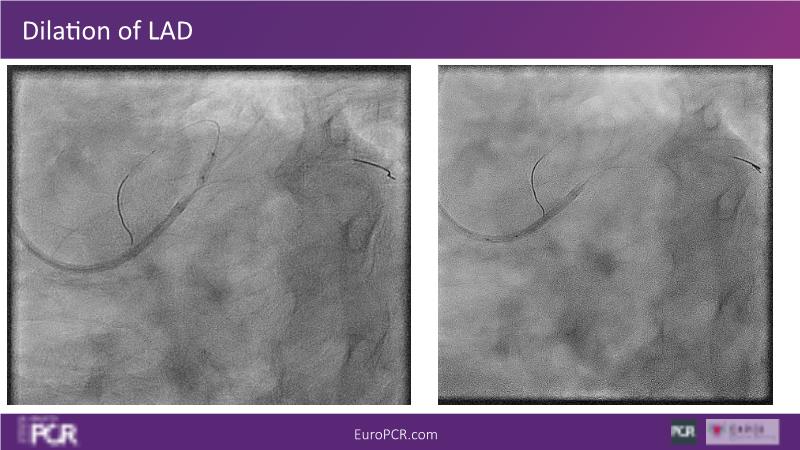

In this session, discover that provisional stenting in routine non-LM bifurcation using Resolute Onyx DES yields good mid-term outcomes without side branch intervention, provided the stent is sized to the distal reference and the side branch remains patent after a systematic POT. Learn how bifurcation stenting on a beating heart improves procedural understanding and adaptability. Additionally, explore how FFRangio offers high diagnostic accuracy in assessing physiological bifurcation lesions from angiograms without the need for hyperemia or a wire.